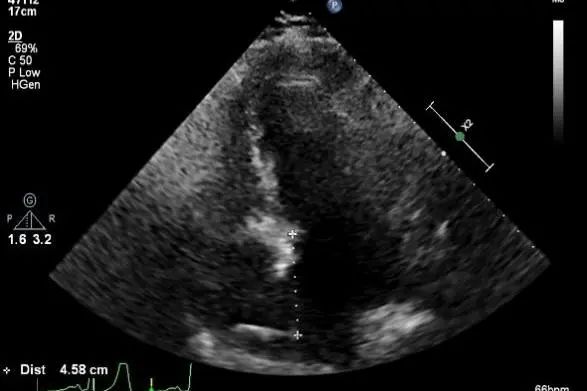

穿刺点距离二尖瓣环4.6cm

二尖瓣联合部切面引导第一枚XTR夹子转向病变区域并逐渐进入左室